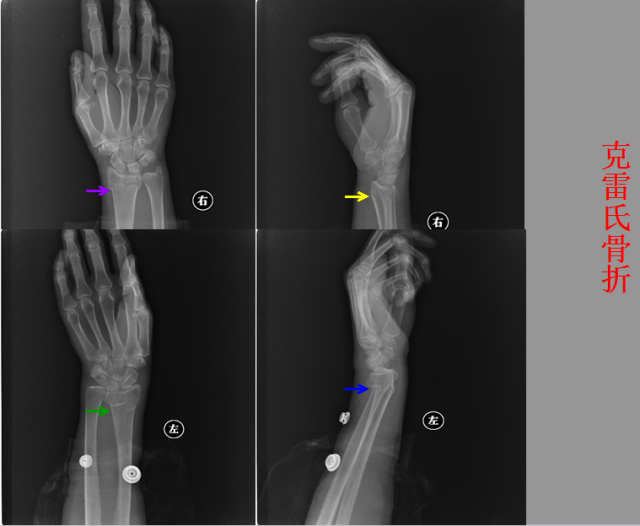

骨折篇

01

定义:骨折{Fracture}是指骨的完整性和连续性的折裂或粉碎。包括创伤性骨折、疲劳性骨折和病例理性骨折。 临床上以创伤性骨折*常见。